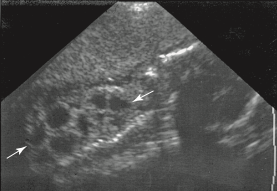

An oblique sonogram of the fetal abdomen most likely demonstrates:

multicystic dysplastic kidney